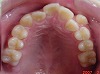

<歯を抜く矯正・歯を抜かない矯正>の写真に示したように、

当歯科医院では顎骨の形を容易に変える事が出来ます。

矯正前

矯正後